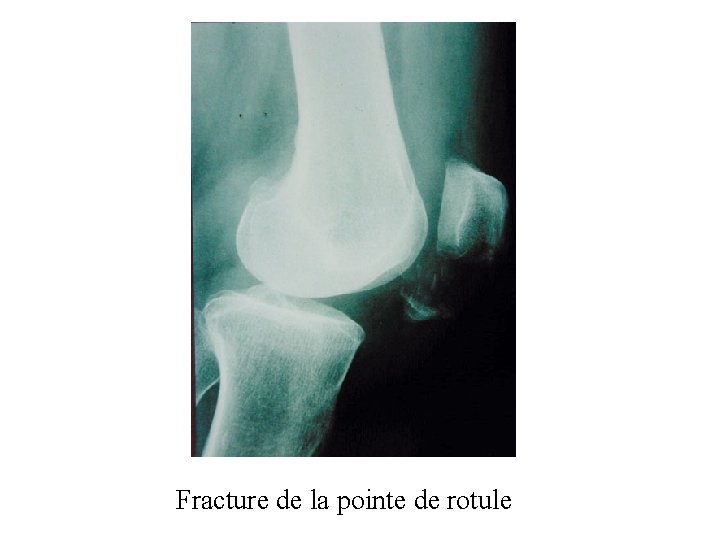

Fracture de la pointe de rotule